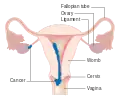

Stage I choriocarcinoma

Stage I choriocarcinoma Stage 2 choriocarcinoma